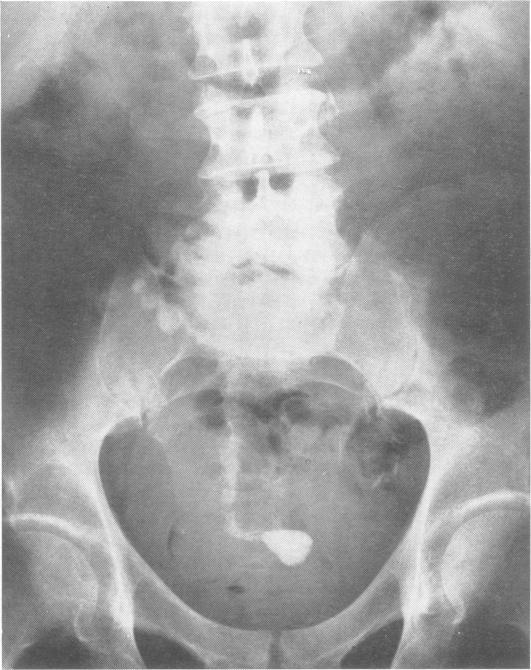

Tabetic spinal arthropathy. Two cases with motor symptoms due to root compression.

Br J Vener Dis. 1960 Dec;36(4):261-5. doi: 10.1136/sti.36.4.261.